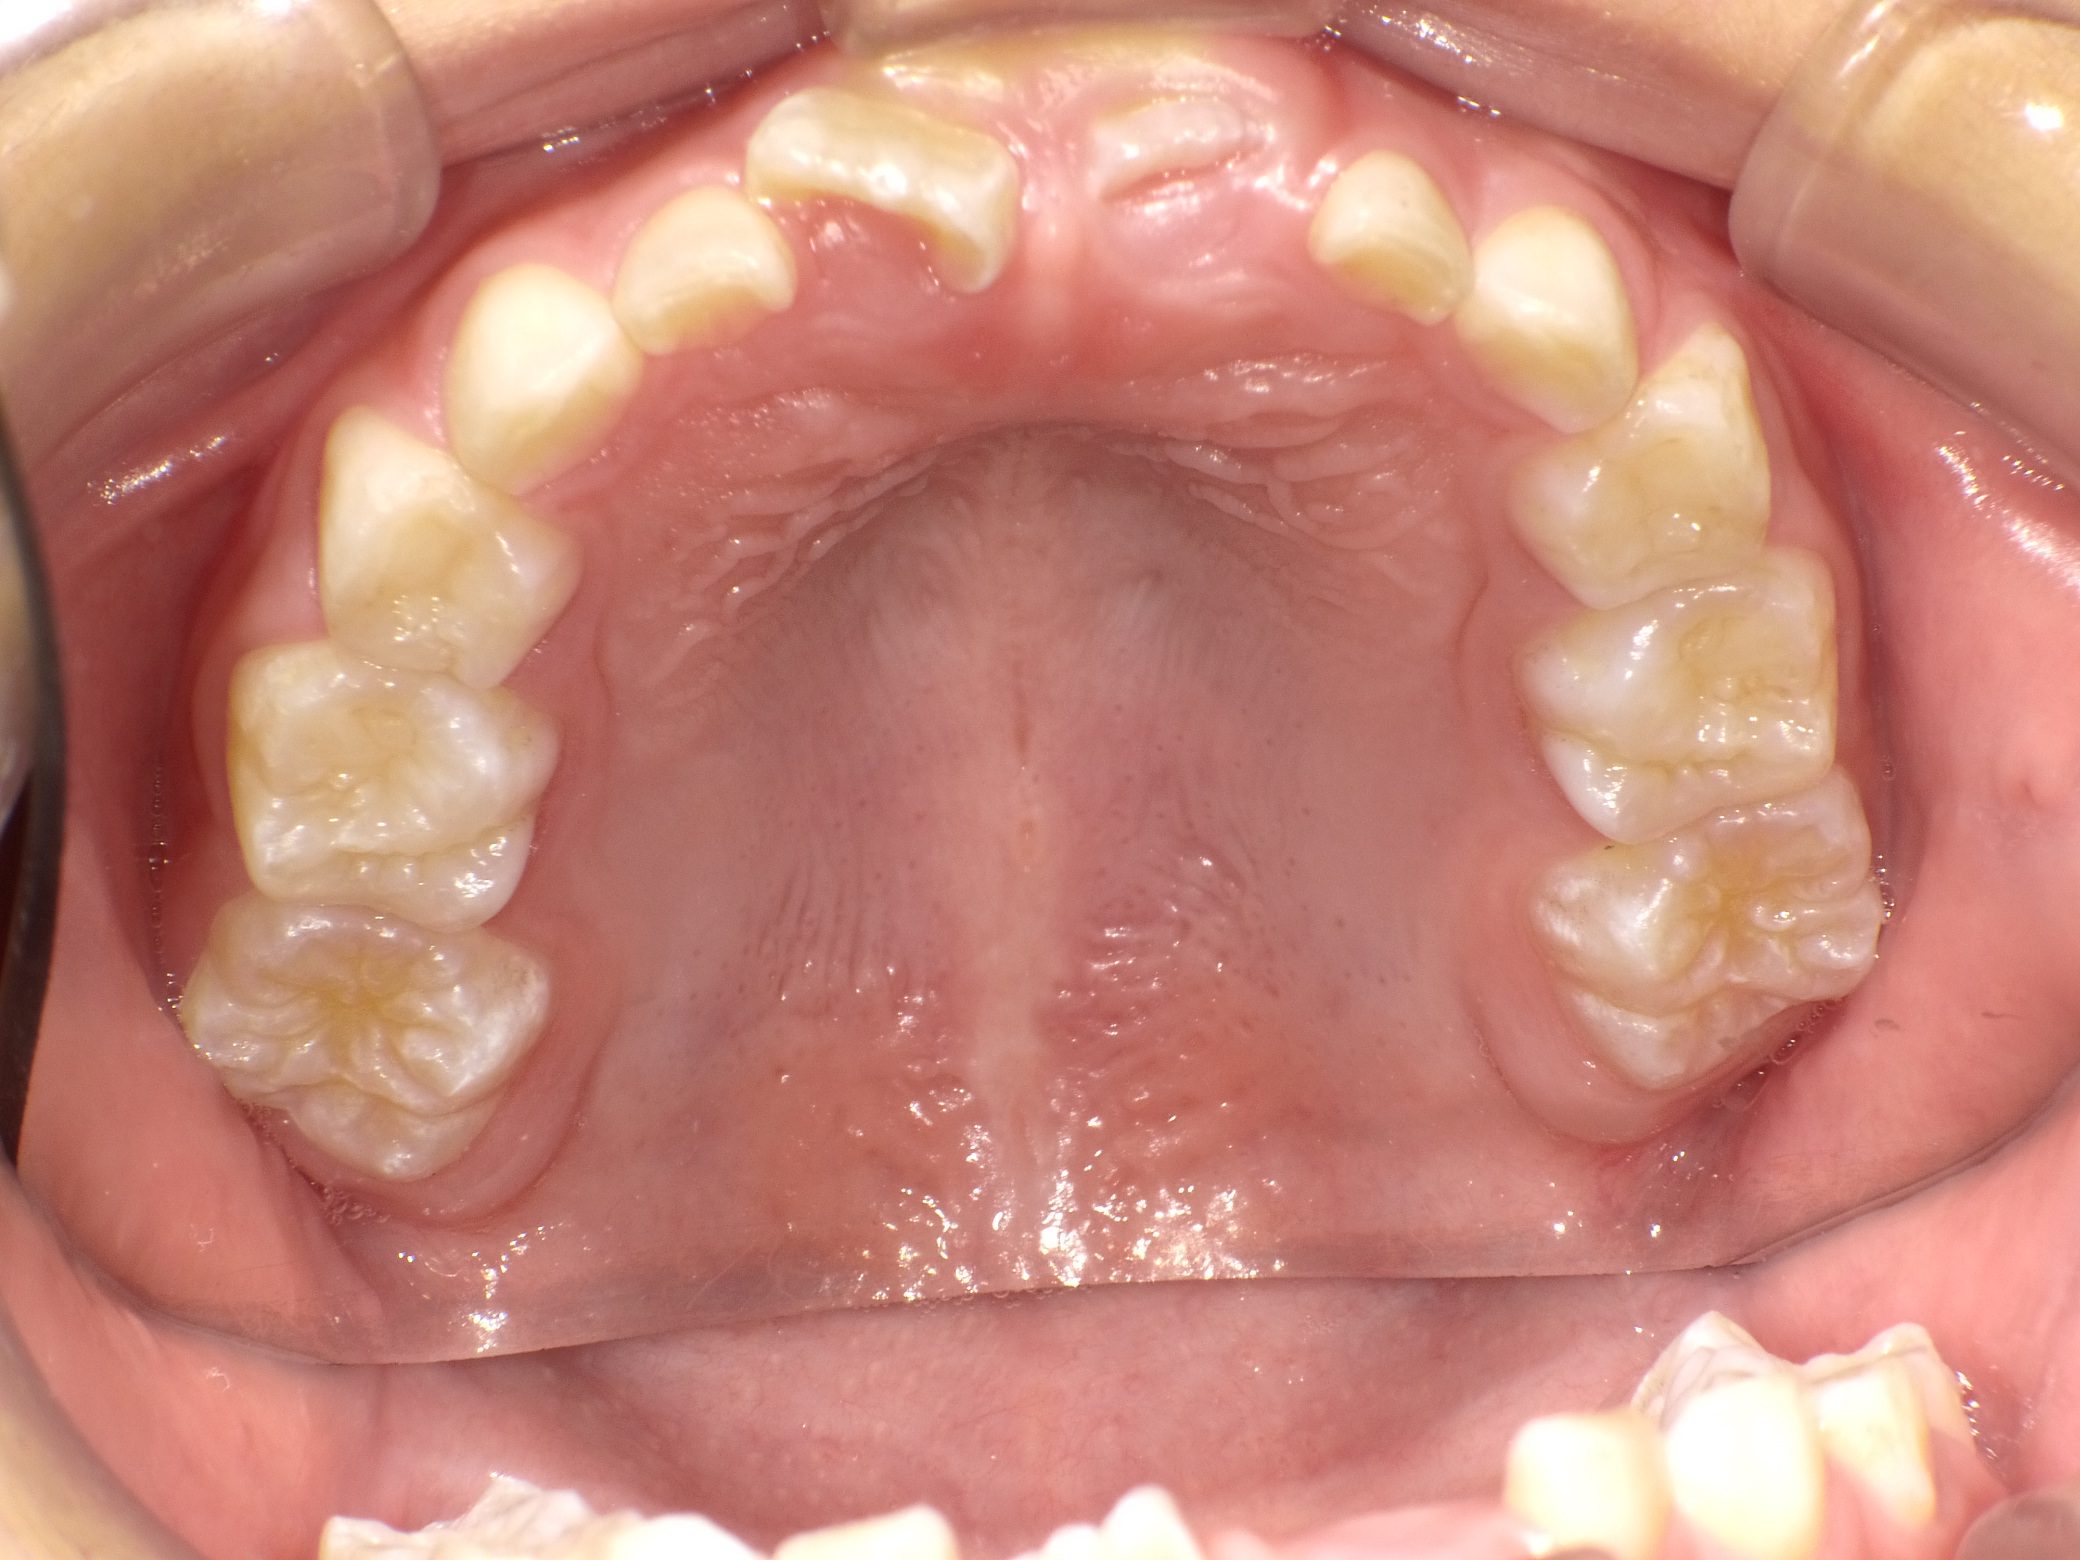

【小学生】マイオブレース矯正 受け口を改善 ④

小学生で開始

マイオブレース

受け口

非抜歯

1期治療のみで改善

Before

After

治療期間

2年

治療開始

8歳

種類

マイオブレース矯正

使用装置

機能矯正装置

コメント

機能矯正装置を利用

しっかり取り組んでくれたので 治療後3年 後戻りはありません